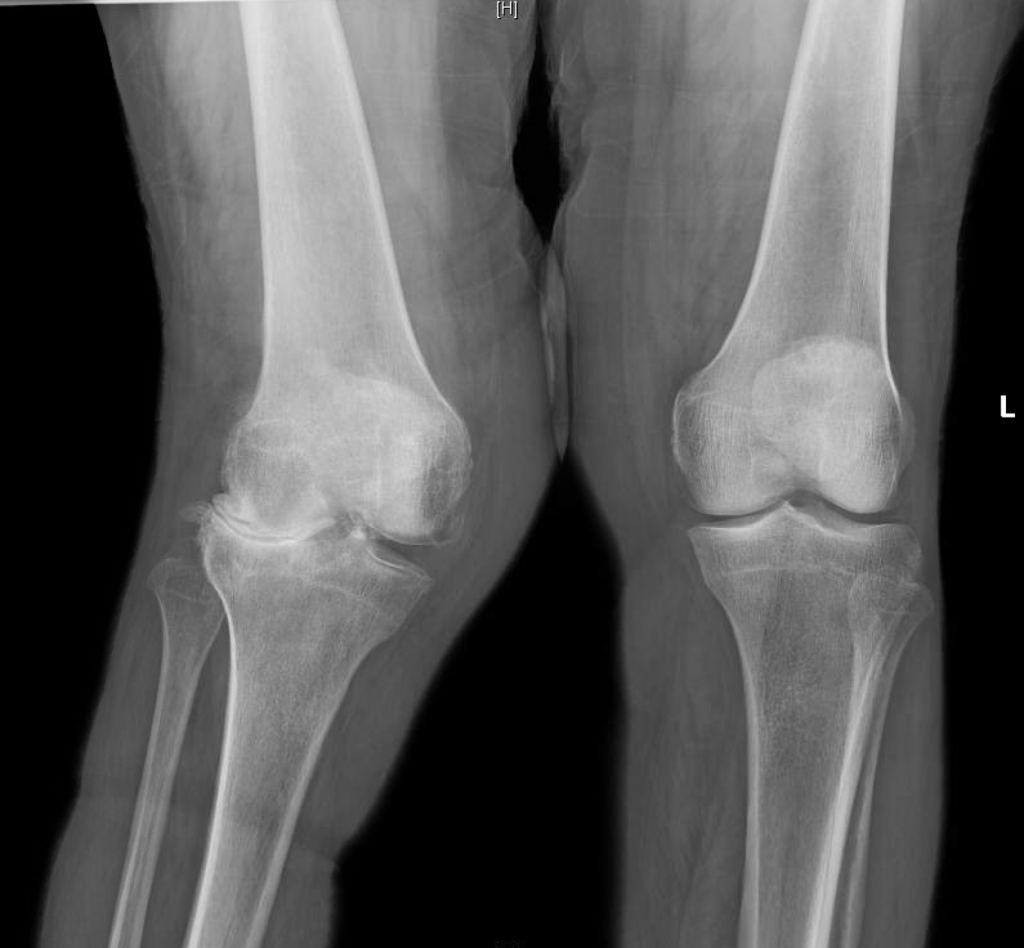

Preoperative radiographs demonstrating bilateral severe valgus knee Lock Knee Deformity Find out about the common causes of a knee locking up and. Knee locking is where the knee gets stuck and can't bend or straighten. The acute locked knee requires urgent assessment and treatment, as prolonged positioning in flexion may lead to permanent deformity and contractures as a result of. It appears most frequently in young children. This article outlines. Lock Knee Deformity.